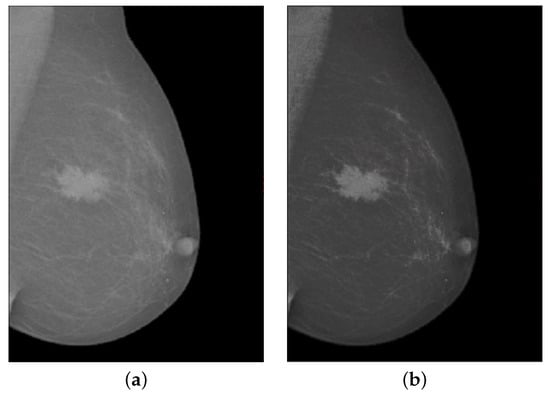

Figure 3 shows the contrast enhancement of the input image. In Figure 3a, the source mammogram image having a tumor is not visible as the tumor in the breast image has no sharp edges. Whereas in Figure 3b image shows that after using the modified contrast enhancement approach, the image gradient has been significantly improved and the disease part is prominently highlighted in the breast mammogram image. Upon closing of this phase, the proposed approach moves to the third phase, which is detailed in the next subsection.

Figure 3.

The mammogram image for contrast enhancement. (a) source image, (b) contrast enhanced image using modified CLAHE.